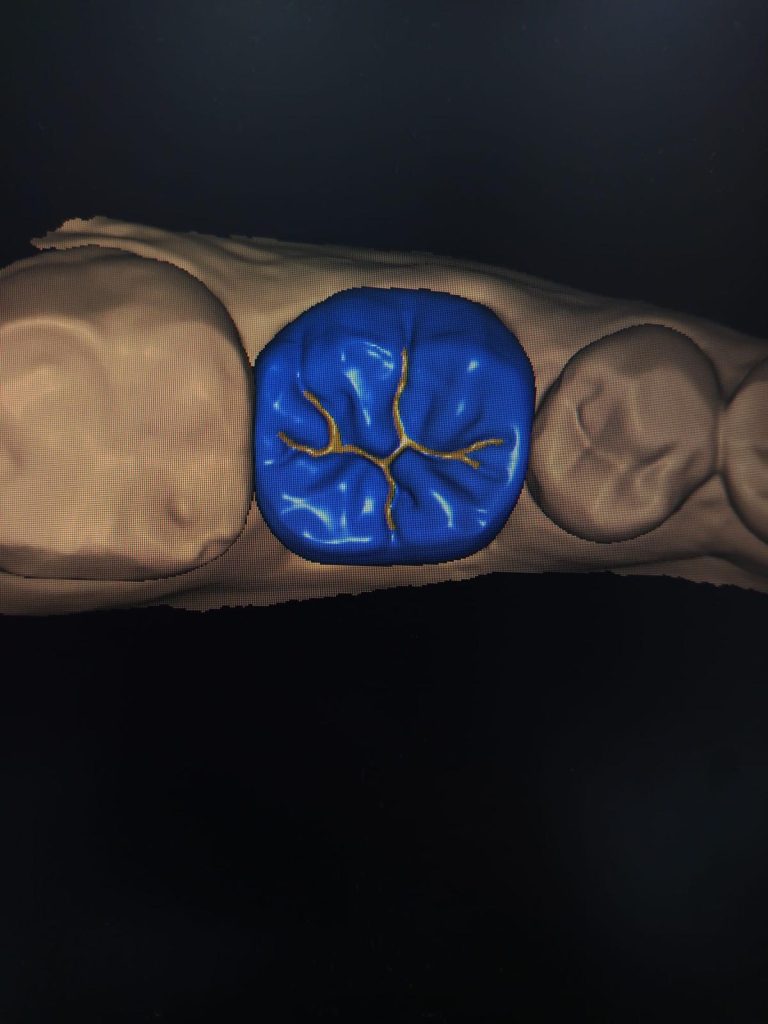

MONOLITIK ZiRKONYUM INLEY ONLEY

MULTILAYER ZiRKONYUM INLEY ONLEY

ZIRKONYUM INLEY ONLEY & LAMINATE